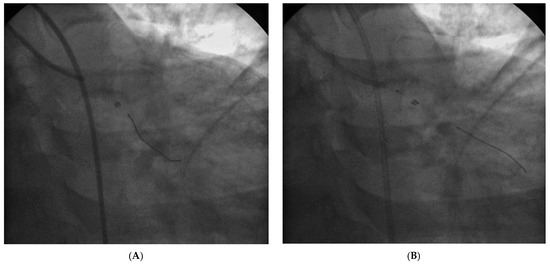

Revascularization After Removal of Broken Catheter from Left Circumflex Coronary Artery

Case report